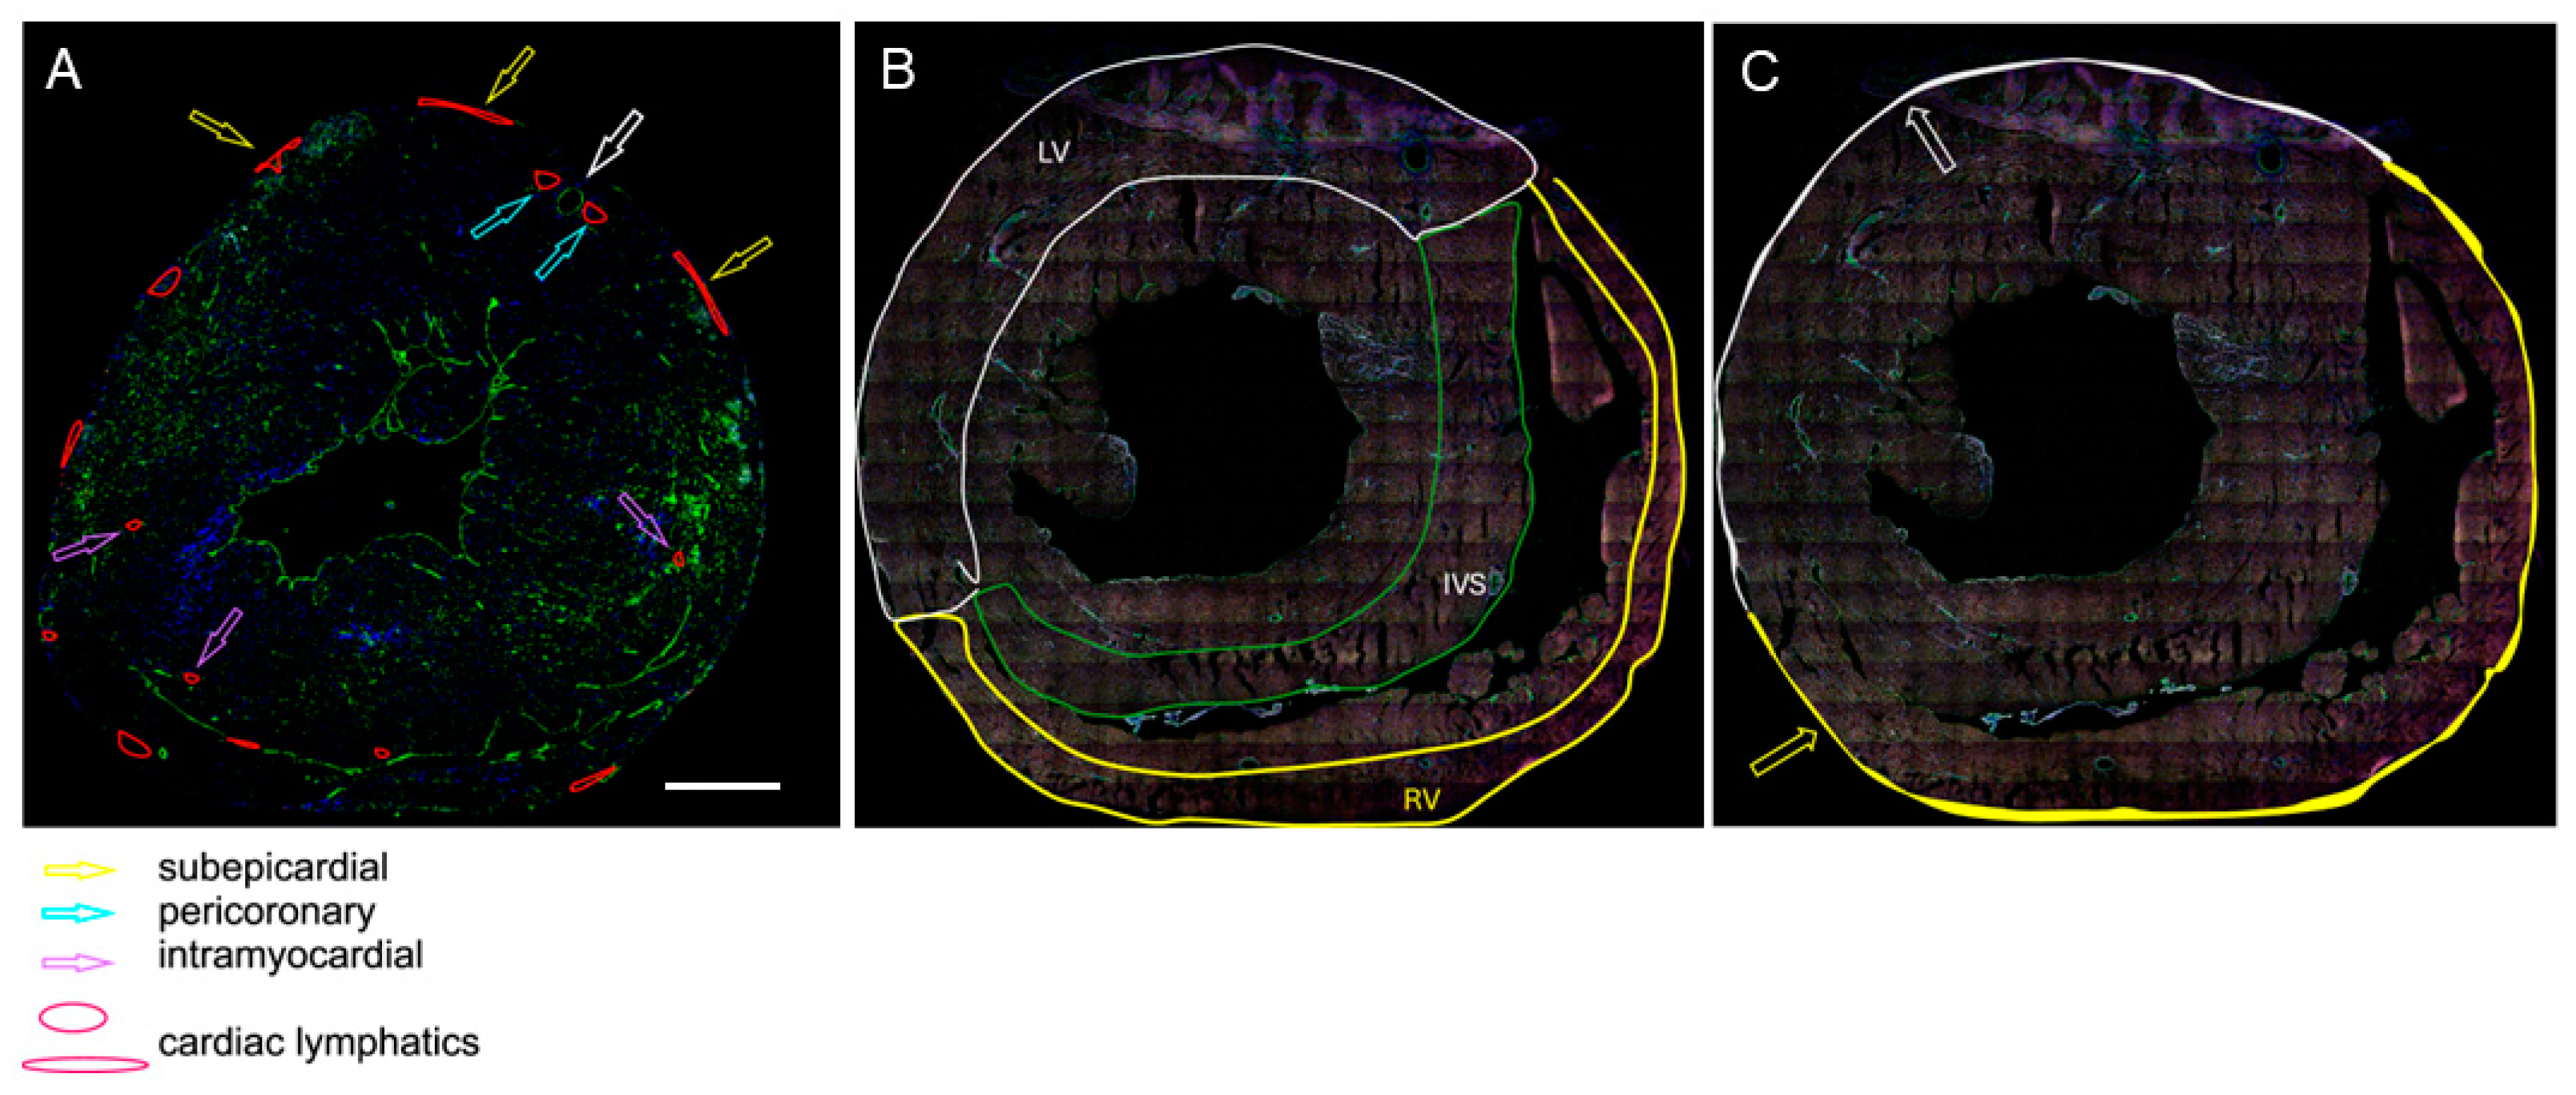

- As the ratio of the number of LyVs to the number of cardiomyocytes within the same area of tissue. The assessment was carried out at three different locations: the outer half of the left ventricular wall, the outer half of the right ventricular wall, and the half of the interventricular septum (IVS) facing the right ventricle (RV). These areas were selected because cardiac LyV in mice are only located in certain regions of the heart, as shown in the schematic drawings in Figure 1A,B.

- As the density of the subepicardial and intramyocardial LyVs, which was calculated as the number of LyVs per area of tissue (expressed in mm2) and the density of pericoronary LyVs, which was calculated as the ratio of the number of pericoronary LyVs to the number of all cross-sectioned coronary arteries in a given tissue section (a coronary artery is marked with the white-edged arrow in Figure 1A). The terms subepicardial, pericoronary, and intramyocardial were understood as follows: subepicardial LyVs (enclosed with white and yellow lines and marked with white- and yellow-edged arrows in Figure 1A,C) were located within the subepicardial area (defined as the distance between the epicardial mesothelium and the myocardial border of mesenchymal tissue); pericoronary LyVs (marked with blue-edged arrows in Figure 1A) were immediately adjacent to coronary vessels; and intramyocardial LyVs (marked with violet-edged arrows in Figure 1A) were in neither of these locations, instead being scattered in the myocardial wall.